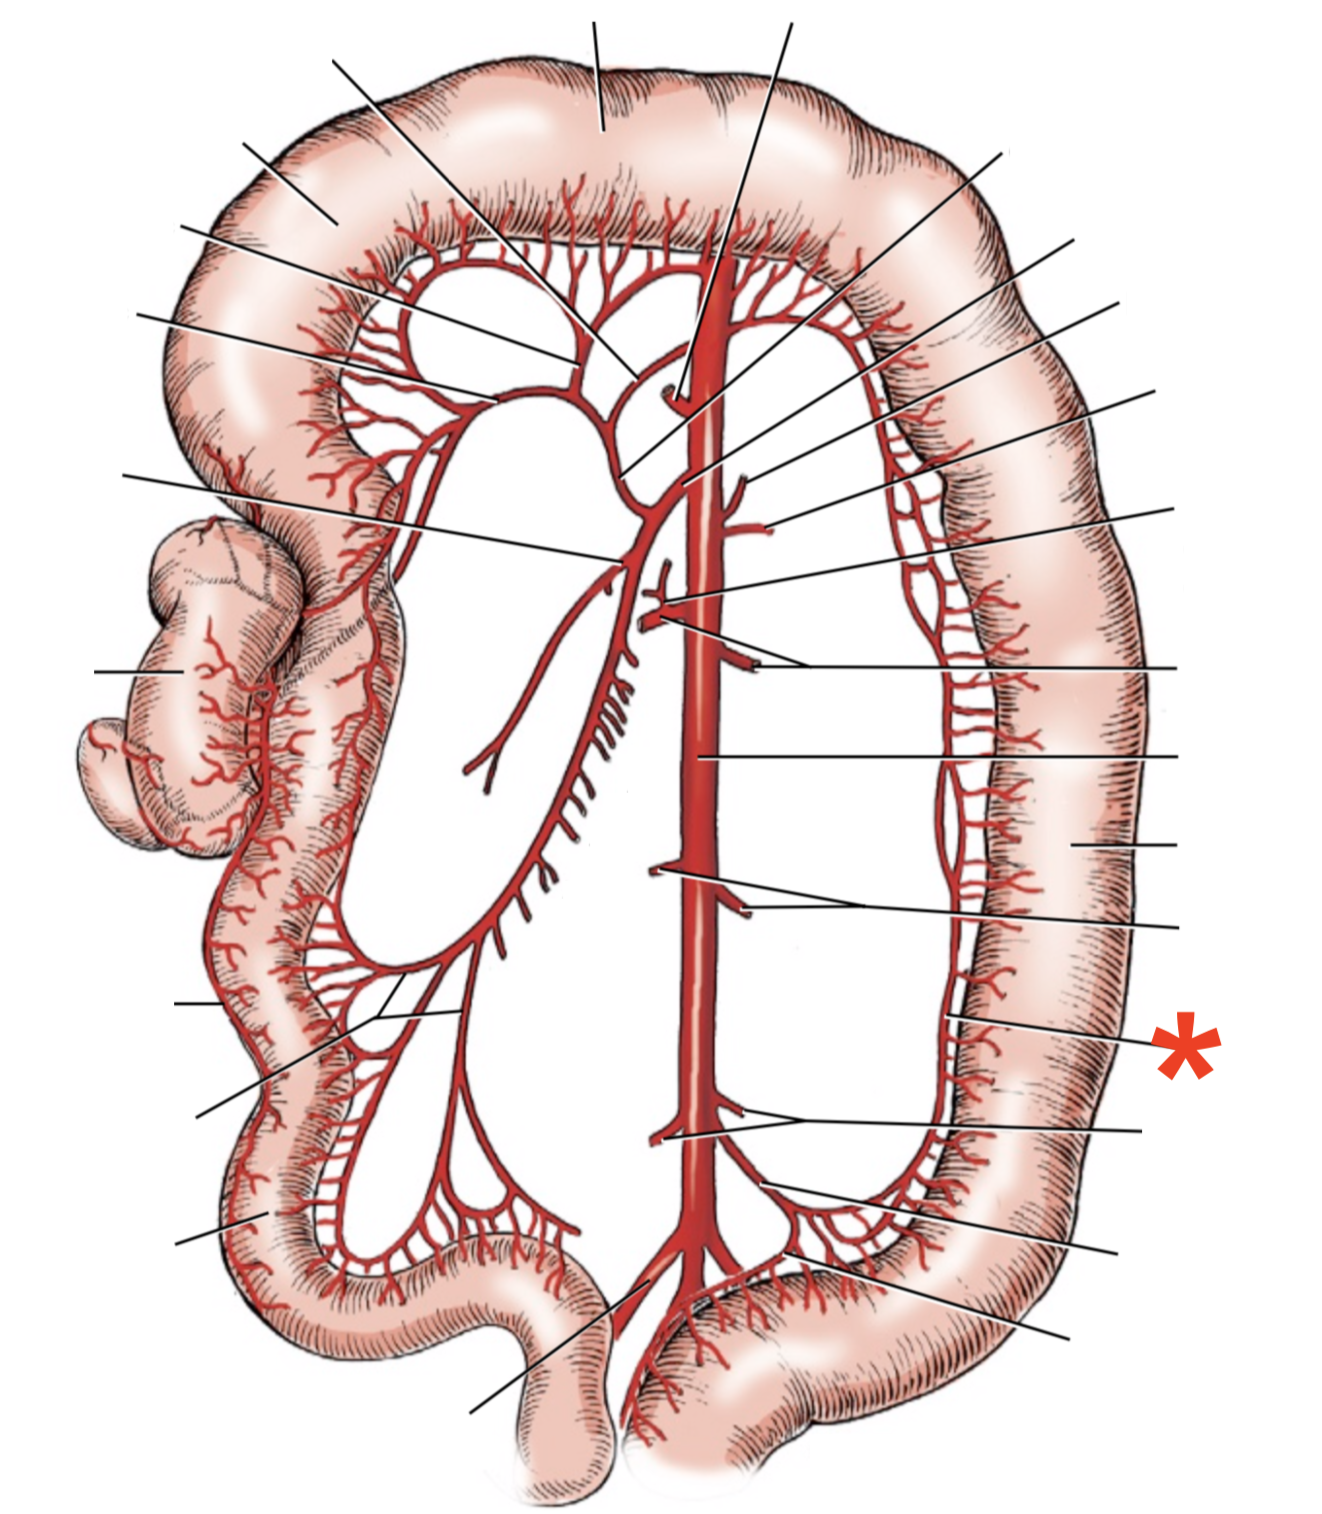

A

A. mesenterica cranialis

A

A. mesenterica caudalis

A. pancreaticoduodenalis caudalis

A

Aa. jejunales

A

A. ilei

- Anastomises with r. ileus mesenterialis a. iliocolica

A

A. ileocolica

A

A. colica dextra

A

A. colica media

A

A. mesenterica caudalis

A

A. colica sinistra

A

A. rectalis cranialis

A

A. ileocolica

**A.** **caecalis**

**R.** **ilei** **mesenterialis**

List the branching of *a.* *mesenterica* *caudalis*

* *A. colica sinistra*

* *A. rectalis cranialis*

List the branches of *a.* *mesenterica* *cranialis*

* *A.* *pancreaticoduodenalis* *caudalis*

* *Aa. jejunalis*

* *A. ilei*

* Common trunk

* A. colica media

* A. colica dextra

* *A. ileocolica*

* *R. ilei mesenterialis*

* *A. cecalis*

* *R. colicus*